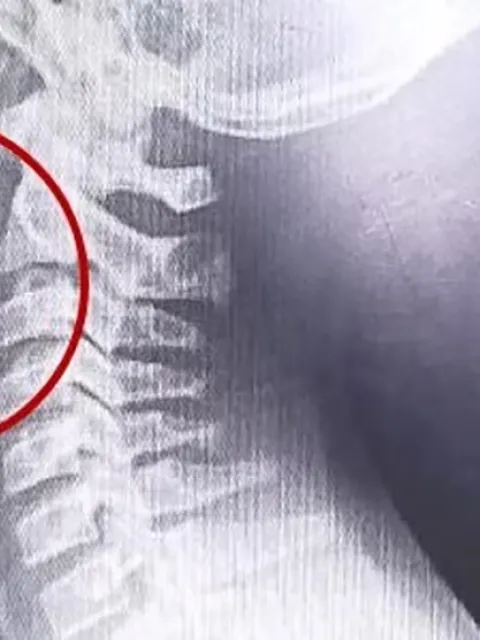

Mediante estudios por imágenes se halló un alambre fino incrustado en la garganta del paciente.

A continuación, se desarrollaron distintos estudios para descartar la presencia de infecciones o bacterias, cuyos resultados resultaron negativos. La clave para entender el cuadro apareció tras la realización de estudios por imágenes: las placas evidenciaron la presencia de un objeto extraño alojado en la vía aérea superior.

El parte médico consignó que el paciente ingresó "clínica y hemodinámicamente estable, afebril, vigil, reactivo, normohidratado y normoperfundido", según el medio local. Luego de una interconsulta con el servicio de otorrinolaringología, se resolvió su ingreso urgente a quirófano. Allí, el equipo médico halló un alambre fino incrustado en la garganta del adolescente, situación que no había sido advertida previamente.